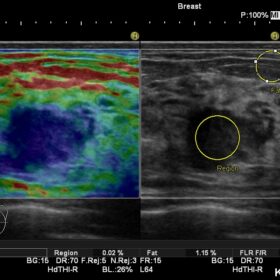

Cardio 2D, Color, PW, CW and TDI mode

Radiology 2D, Color, PW and Elasto mode

The Ultra BE, an ultrasound-specific digital signal processor is at the core of the Noblus. Achieving advanced beam formation and sophisticated image processing. Migrated from the high-end HI VISION cart-based systems, this technology brings reliable diagnostic performance. That will ensure a smooth workflow. It’s powerful transmission and reception capability enables functions. Such as Real-time Tissue Elastography (RTE) and dynamic Contrast Harmonic Imaging (dCHI), modalities that can offer increased diagnostic confidence.

Using Hitachi’s own broadband technology to increase the harmonic frequency bandwidth, the High definition dynamic Tissue Harmonic Imaging (HdTHI) mode gives you both high resolution and excellent penetration. The HI Rez+ tissue adaptive filter optimises contrast resolution, border enhancement and noise suppression without reducing frame rate, and the HI Com, real-time spatial compounding technology, that uses multiple beams on transmit and receive, is especially beneficial for clarifying luminal structures

The Noblus offers premium modalities that can be exploited in many different clinical situations. Although compact in design, the powerful engine of the Noblus enables functions such as Real-time Tissue Elastography (RTE), dynamic Contrast Harmonic Imaging (dCHI), real-time 3D with STIC (Spatio-temporal Image Correlation) option and CW Doppler, features previously found only on larger cart-based systems.